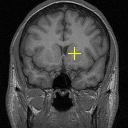

(l) 0.9345

Figure 8: Example comparison among VTN ADD (c/d), VTN DD(e/f), Elastix (g/h), ANTs (i/j) and VoxelMorph-2(k/l). The input images to methods with “” are affinely aligned to a fixed atlas by ANTs and their warped images are transformed backwards according to the affine transformation aligning the fixed image and the atlas for sensible comparison. Columning and coloring are the same as those in Figure 6, except that the fixed image and the moving image are a pair of MR brain scans and that the landmarks are L7, L12 and L15. Best viewed in color.

Figure 8 exemplifies the methods on three pairs of scans. Comparison between our methods and traditional methods proves the applicability of our methods to 3D brain registration. Comparison between ADD and DD shows that integrating affine registration subnetwork is effective.